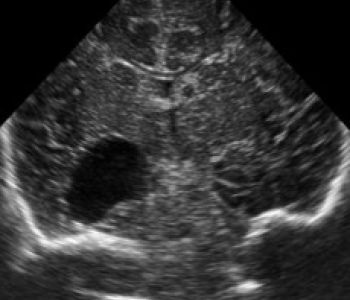

Recién nacido de 35+3 semanas, segundo gemelo de una gestación bicorial-biamniótica que desarrolla en el período fetal un cuadro de crecimiento intrauterino retardado y prenatalmente se detecta una comunicación interventricular, una arteria subclavia derecha aberrante, una arteria umbilical única y una agenesia de ductus venoso.